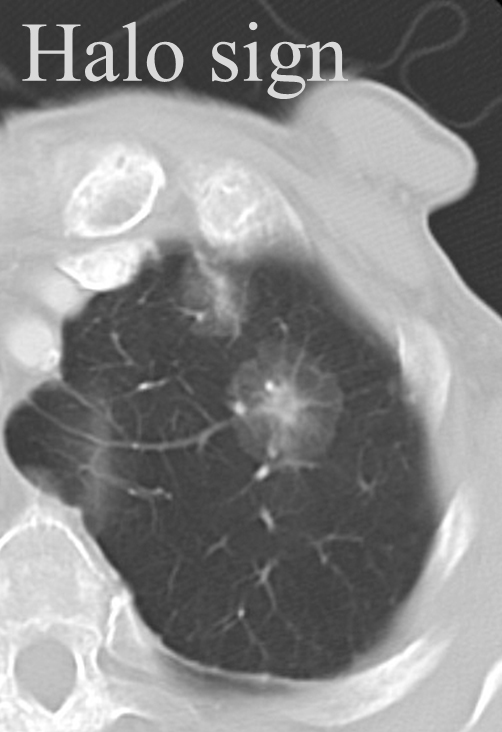

Halo sign